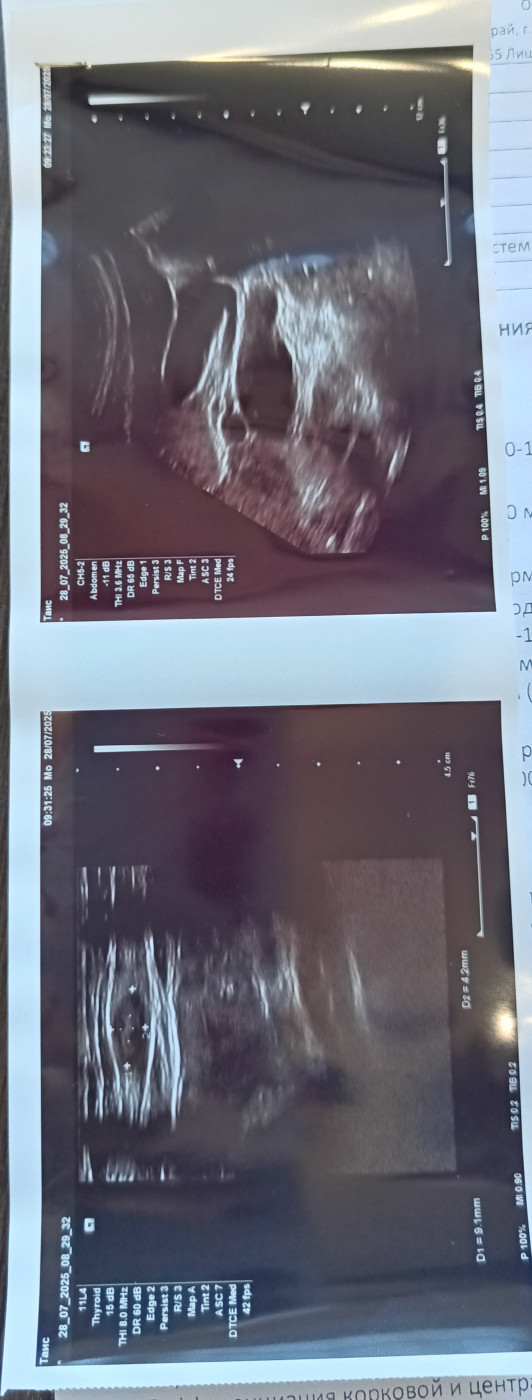

Лимфоузел или нет?   1 ответ

Здравствуйте. Месяца 4 назад рядом со шрамом от аппендицита нащупала уплотнение. Стоя хорошо прощупывается,достаточно плотное маленькое, лежа трудно прощупать. Операция была 17 лет назад. Хирург сказал это липома, узи показало лимфоузел. После обследования прошло 2 месяца, уплотнение не прошло. Я читала, что в это области никак не нащупать лимфоузел. Нормально ли это?